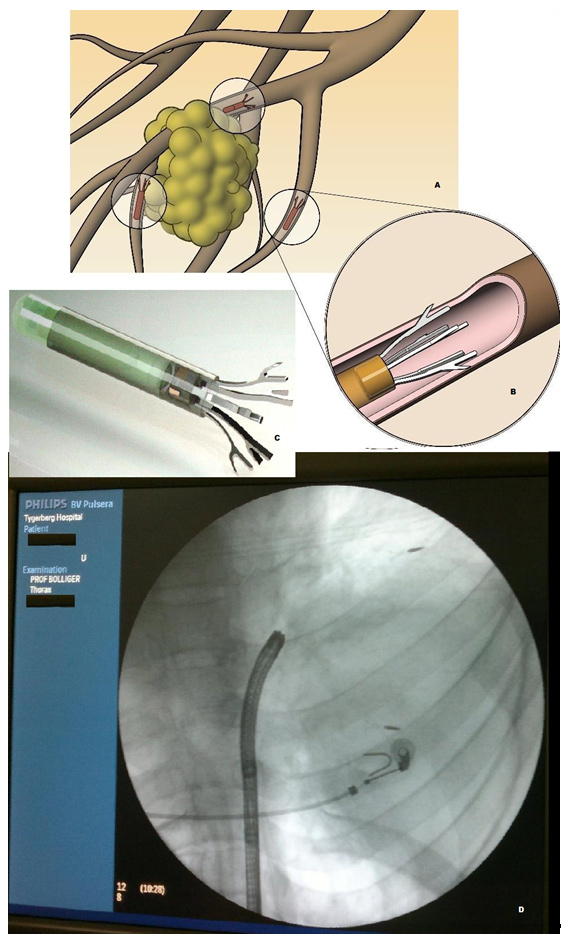

Figure 6

A- Schematic representation of Anchored Beacon® Transponders in situ around the tumor; note: each transponder is deployed in a separate airway; B- Magnified view of the distal end of a transponder showing anchorage in a bronchus; C- The actual Anchored Transponder, approximately the size of a grain of rice; D- Fluoroscopic view of the anchored transponders in situ. In a large right sided lung cancer two out of three transponders have been deployed, one just distal to the ECG electrode, the second one at the distal tumour adjacent to normally aerated lung.

Three dimensional conformal radiotherapy (3D-CRT) is a method of focusing radiation on the tumour, thereby increasing the dose of radiation delivered to the tumour and minimising the volume of irradiated normal lung [38]. However, a major hurdle in effective lung radiation treatment is lung tumour motion during respiration. Current motion management approaches frequently rely on external surrogates and are inaccurate, cumbersome and inefficient. Harada et al. [39] demonstrated feasibility of bronchoscopic implantation of a gold marker into or near peripheral-type lung tumour for real-time tumour-tracking radiation therapy (RTRT). But their accuracy and reliability is limited by low signal-to-noise automatic image recognition algorithms and by non-therapeutic patient radiation from fluoroscopy. An exciting new technique, developed by Calypso Medical Technologies, utilises miniature implanted Beacon® transponders to provide precise, continuous information on the location of the tumour in real time during external beam radiation therapy. The Calypso System, is cleared by the FDA for use in the prostate and post-operative prostatic bed and can potentially be used for real time tumour tracking and localisation in the lungs. Mayse et al. [40] evaluated the feasibility and fixation of electromagnetic transponders bronchoscopically implanted in small airways of canine lungs and compared to results using gold markers. The electromagnetic transponders they used were cylindrical in shape (without anchors) measuring 1.8 mmin diameter and 8.5 mm in length. On excitation by an external source these transponders emit an electromagnetic signal which can then be detected and localised by an electromagnetic array (Calypso 4D Localisation System, Calypso Medical Technologies, Inc.). This localisation information can be used to track the transponder's location in three-dimensional space both before and during radiation therapy beam application. These transponders are bronchoscopically inserted by the use of a polytetra-fluoroethylene (PTFE) implantation catheter.

Mayse et al. [40] demonstrated that bronchoscopic implantation of the electromagnetic transponders into the small peripheral airways was feasible but was limited by the fact that a substantial portion of the successfully implanted transponders and markers dropped out of the lung over the next 60 days. Currently a first in man multicentre study which was started in Cape Town, South Africa and includes among other sites, the Division of Pneumology, University Hospital Basel, Switzerland, is evaluating the use of anchored transponders in lung cancer patients receiving radiation therapy. Bolliger et al. [41] presented early results on clinical experience and safety of implanted anchored Beacon transponders in lung cancer patients. Three anchored transponders were successfully implanted in each patient after identifying suitable implantation sites in small airways in proximity to the lung primary on CT chest. No patient had developed pneumonia, pneumothorax or adverse pulmonary symptoms as a result of implantation of the anchored transponders. All the anchored transponders were subsequently used for tumour localisation and tracking by the Calypso System. Follow-up imaging revealed good positional stability and no migration of the anchored transponders. Further developmental work is under way. Whether these fiducial markers revolutionise the treatment outcomes in patients receiving radiotherapy will be determined only by further studies.